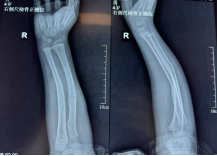

阳光讯(记者 郑亚雷 通讯员 曾雪琴)2月9日,4岁的小嘉佑被父亲紧紧抱在怀里来到了西安市红会医院手法复位室,孩子的右前臂明显肿胀、变形。接诊的张晓星医生立即进行体格检查,并安排影像学检查。X线片显示,小嘉佑为典型的儿童尺桡骨双骨折,骨折线横贯前臂中下段,骨折端不仅存在明显的侧方移位,还伴有一定程度的成角畸形。

复位后即刻复查的X线片正位片显示,桡骨与尺骨骨折端对位良好,侧方移位完全纠正;侧位片显示掌背侧成角畸形已有效矫正,力线接近正常。